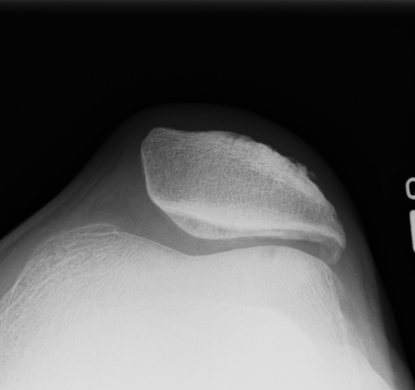

Lateral Xray

1. Assess Patella Alta

B. Blackburn-Peele ratio / Best and Most accurate

Distance between tibial and patella articular surface

- divided by patella articular surface

- patella alta > 1